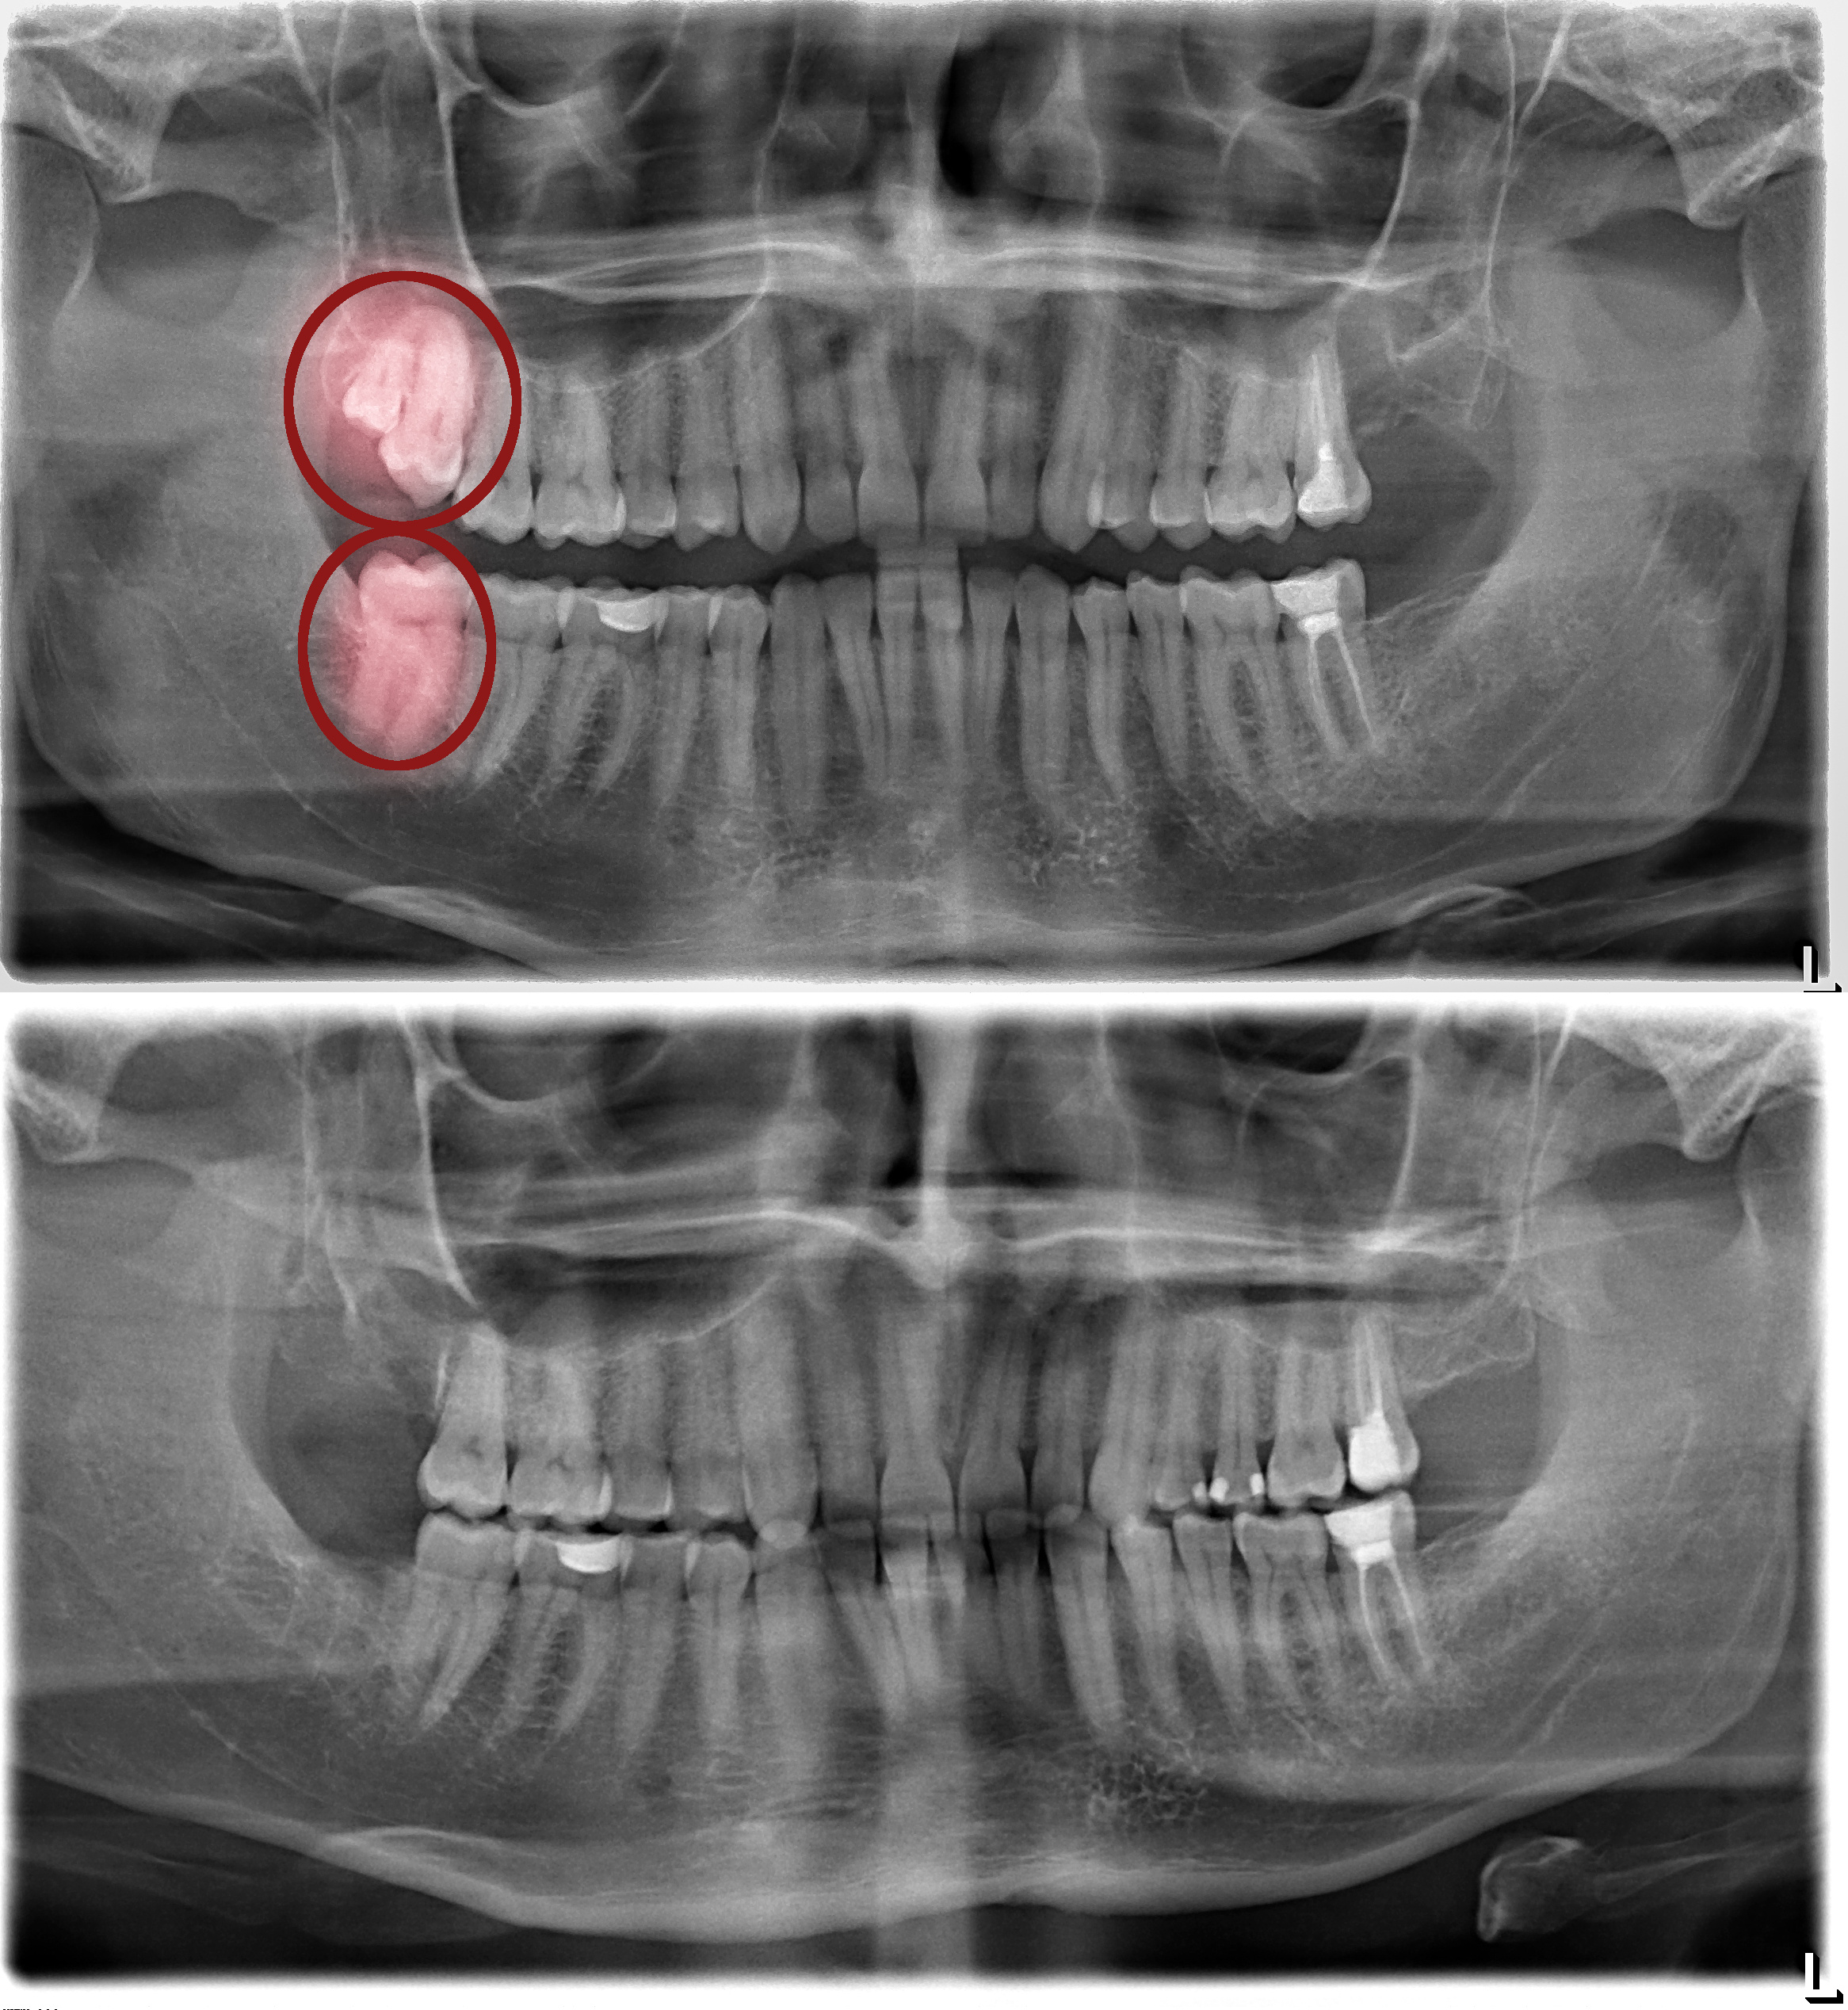

• Pemeriksaan Mendalam: Kami melakukan pemeriksaan dengan X-ray untuk memastikan posisi dan kondisi gigi bungsu secara akurat.

Sebelum & Sesudah Tindakan (Before – After)

Sumber: https://santarosaoralsurgery.com/wp-content/uploads/2021/08/santa-rosa-impaction-bracketing-1.jpeg